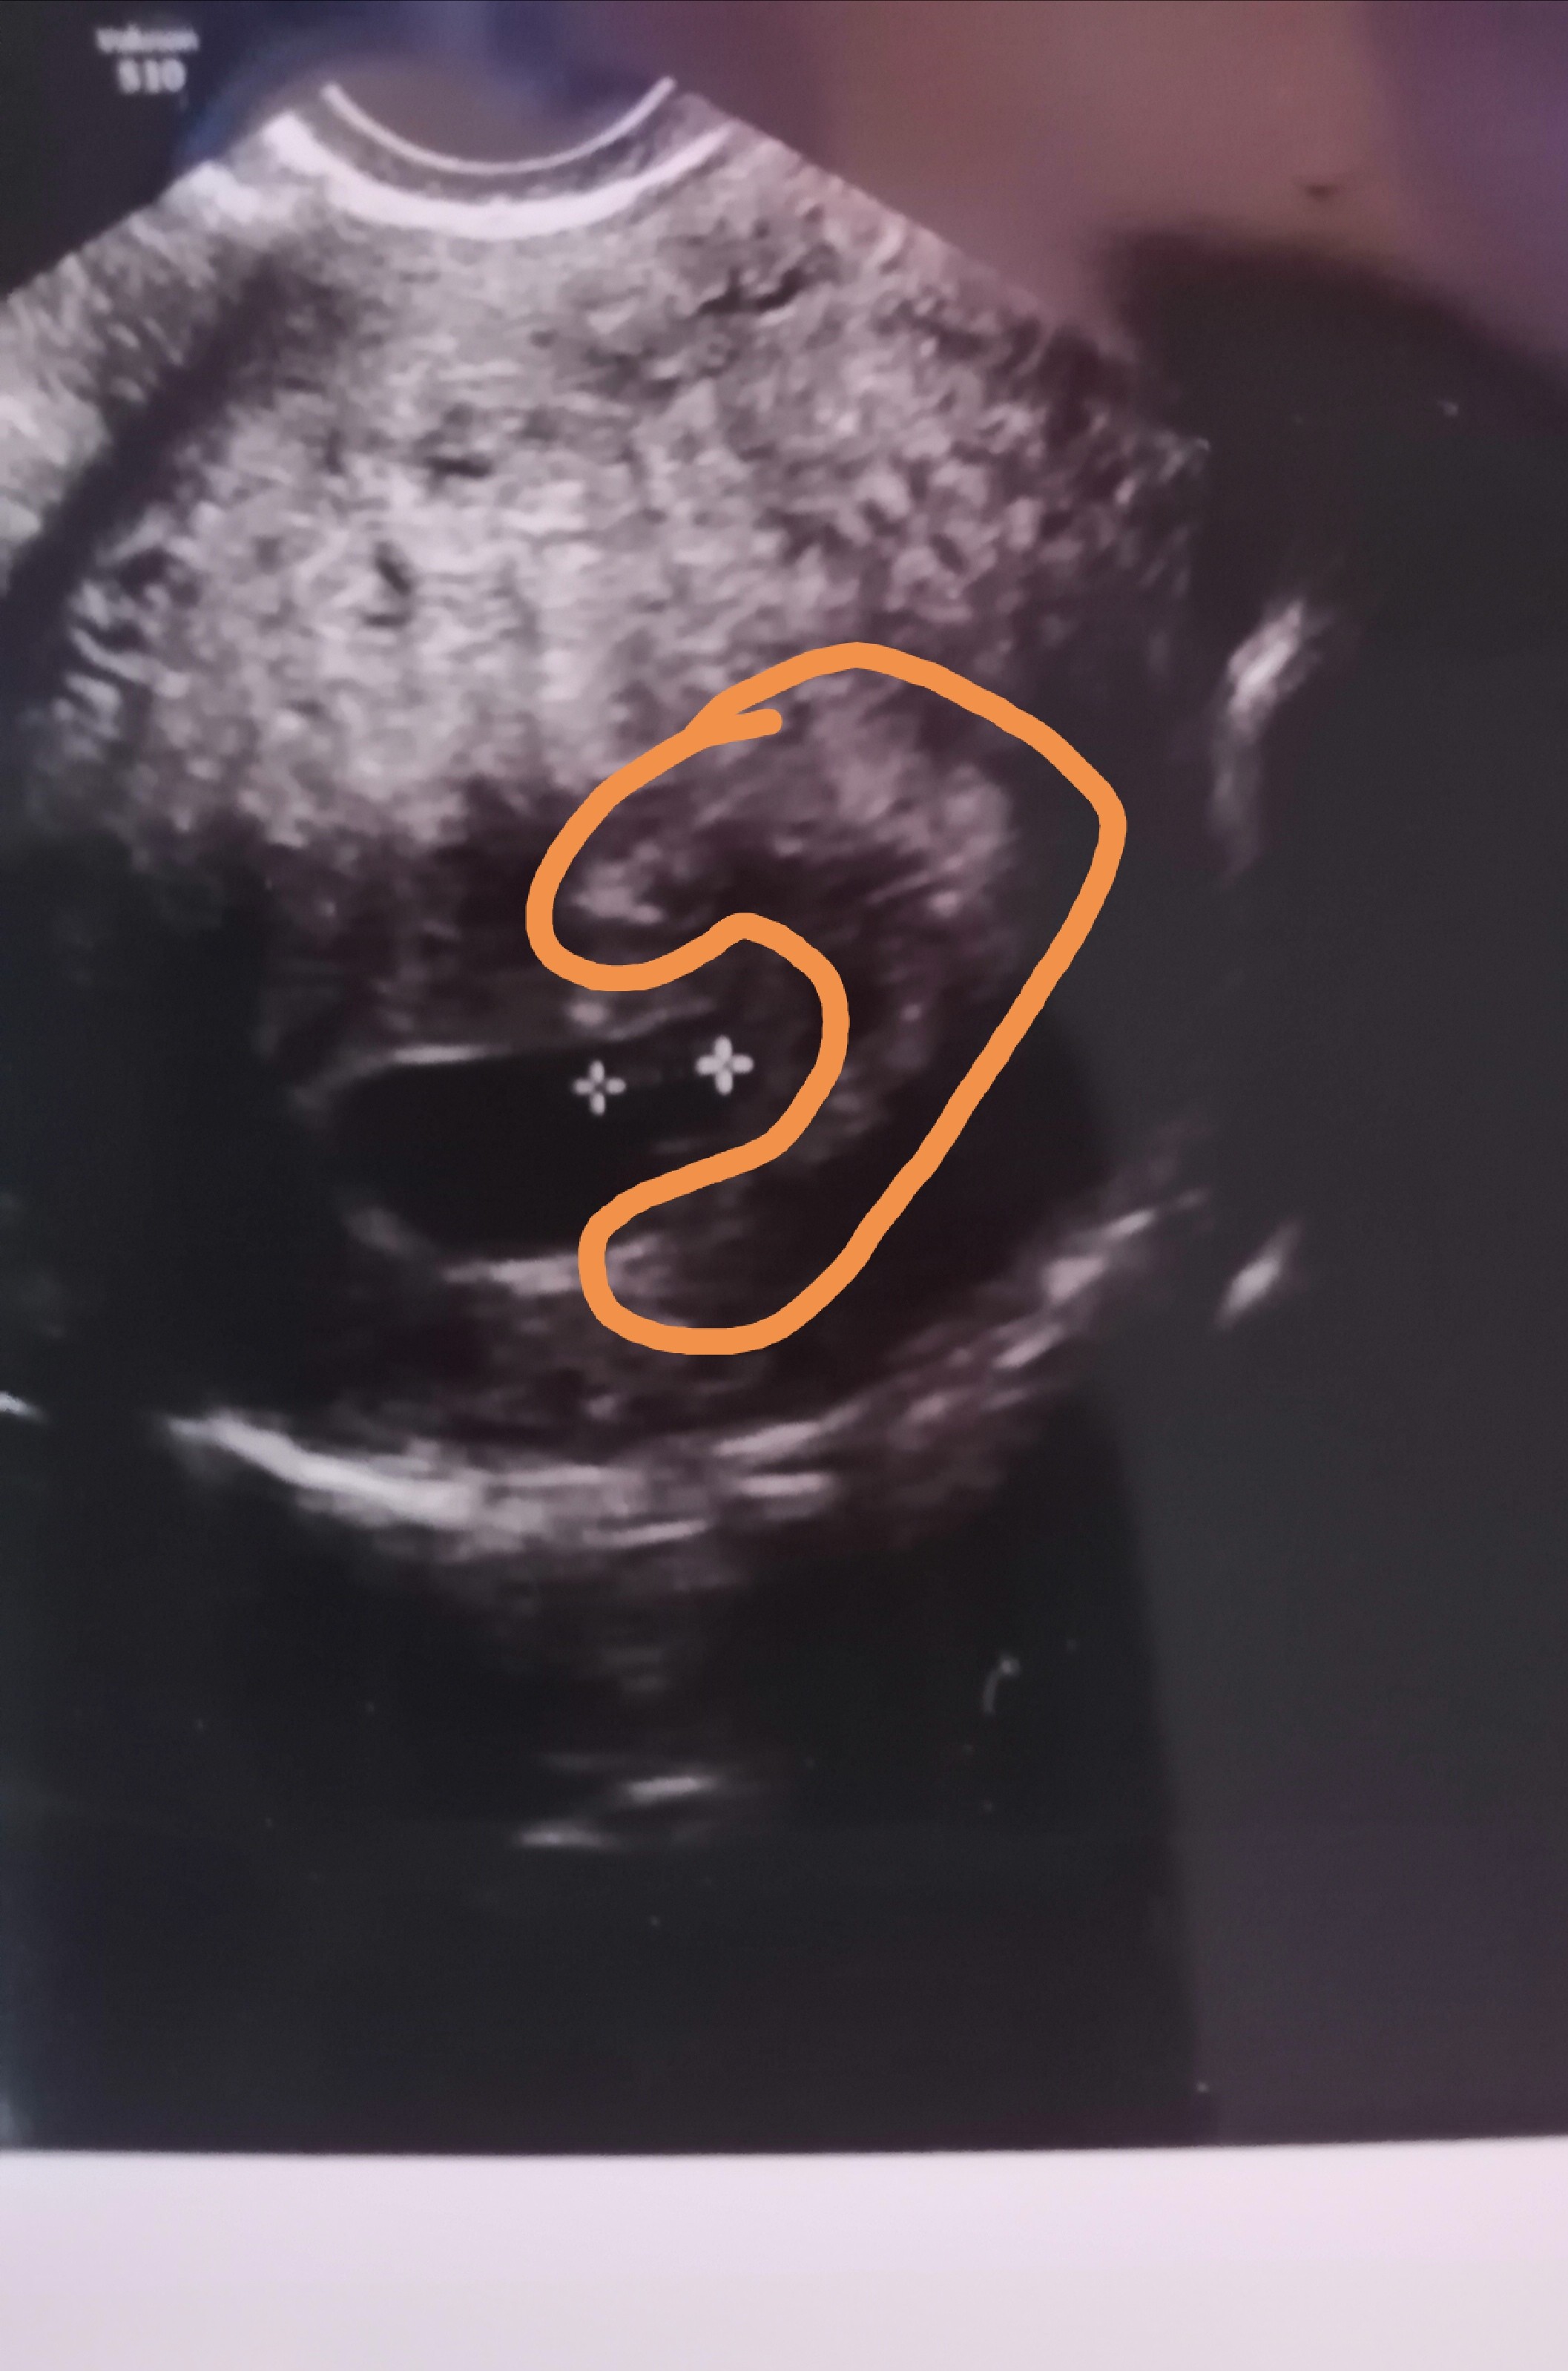

chciałabym żeby całe było zrobione nie tylko środek zarodkaTakie może być? Zaskoczyłaś mnie że z 7tc![]()

Mam jeszcze takie z 7tc ale ja tam nic nie widzęchciałabym żeby całe było zrobione nie tylko środek zarodka

Jej kochana lekarz tak też coś tłumaczył na 3d/4d ale nie byłam w szoku bo tak marzy mi się córciaMoim zdaniem dziewczynka. Na tym pierwszym zdjęciu są takie dwie kreseczki obok siebie, wzdłuż siebie idą a jak jest chłopiec ta firma idzie ku górze![]()